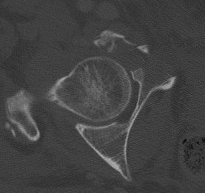

B. CT subchondral arc

- 10 mm below subchondral bone of roof

- similar to xray roof arc measurements

3. Stability / Concentric reduction

Subluxation

- incongruency between the head and the roof

- poor clinical results are obtained in more than 50% of fractures in which the head is subluxed

- may also have an element of dynamic instability, with certain posterior wall fractures

Any subluxation on CT demonstrates clinical instability

- fractures affecting 40% or more of the posterior wall are usually associated with instability

- fractures less than 40% should be screened for stability under II